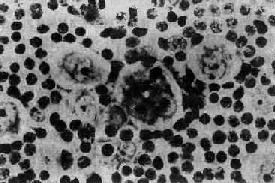

镜下,淋巴结的正常结构破坏消失,由组织取代。组织内的细胞成分多样,有些是肿成分,有些是非肿成分。组织中有一种独特的多核巨细胞,体积大,直径约15~45μm,椭圆形或不规则形;胞浆丰富,双色性或呈嗜酸性;核大,可为双核或多核,染色质常沿核膜聚集成堆,核膜厚。核内有一大的嗜酸性核仁,直径约3~4μm,周围有一透明晕。这种细胞称为Reed-Sternberg细胞(R-S细胞)。双核的R-S细胞的两核并列,都有大的嗜酸性核仁,形似镜中之影故称镜影细胞(图11-1)。这些双核和多核的R-S细胞是诊断HD的重要依据。

何杰金病示镜影细胞

图11-1 何杰金病示镜影细胞